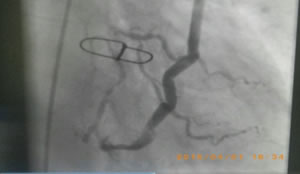

図7:一本の大伏在静脈をグラフトとして使い、3箇所に分けて吻合した例

この術式は「sequential bypass (シークエンシャルバイパス)」と言います。

非常に難度が高いです。